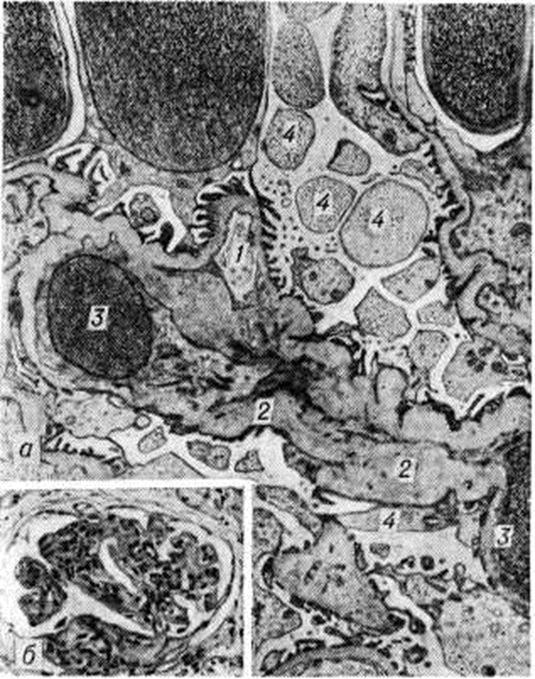

Реже ему предшествуют другие причины: пневмонии, пищевые токсикоинфекции, охлаждение, введение вакцины, сывороток, медикаментов и так далее. Реже ему предшествуют другие причины: пневмонии, пищевые токсикоинфекции, охлаждение, введение вакцины, сывороток, медикаментов и так далее. Типирование стрептококков, выделенных из зева больных Гломерулонефрит, показало, что в 78% случаев обнаруживается тип 12β-гемолитического стрептококка группы А. Преобладание 12 типа стрептококка отмечается как в спорадических случаях, так и при вспышках заболевания. В жарких странах развитию Гломерулонефрит особенно часто [в 85% случаев, по данным Диллона (Н. С. Dillon), 1967] предшествуют кожные болезни (пиодермия, импетиго, рожа); у таких больных, как правило, высеиваются пиогенные стрептококки. В сыворотке крови больных Гломерулонефрит наиболее часто обнаруживаются антитела к типу 12 стрептококка. Почти у 51% больных острым Гломерулонефрит стрептококковые антигены обнаруживаются в крови и выявляются в клубочках при иммунофлюоресцентной микроскопии [Сигал (В. С. Seegal), 1965; Андрес (G. A. Andres) с соавторами, 1966]. Часто обнаруживаются также антистрептолизин-О, антигиалуронидаза и антистрептокиназа. Однако постстрептококковый острый Гломерулонефрит с 50-х годы стал встречаться реже, что связано в значительной степени с применением мощных антибактериальных препаратов. Теснее связан со стрептококковой инфекцией Гломерулонефрит при подостром септическом эндокардите, что может проявляться не только классическим очаговым эмболическим нефритом [Лелейн (М. Н. F. Lohlein), 1910], но и диффузным поражением почек. Частота поражения почек при подостром септическом эндокардите может быть высокой — до 50%, при ревматизме (по секционным данным) — до 10,5%. Описан Гломерулонефрит и при стафилококковом эндокардите. Пневмонии осложняются Гломерулонефрит в 1—3% случаев. Роль брюшного и сыпного тифа, малярии в развитии Гломерулонефрит невелика. При малярийном нефрите находят отложение малярийного антигена в клубочках в составе иммунного комплекса наряду с иммуноглобулинами, комплементом, фибрином. При туберкулёзе клинический, картина Гломерулонефрит может оказаться ведущей. По данным В. В. Сура, А. М. Вихерта (1966), мембранозный Гломерулонефрит легко воспроизводится у животных при введении микобактериального адъюванта, то есть стимулятора процессов иммуногенеза (смотри полный свод знаний Адъюванты). Гломерулонефрит при туберкулёзе у человека описан Б. М. Коваливом и В. Ф. Подуговским (1957). Гломерулонефрит при сифилисе, протекающий обычно по нефротическому типу, редок. К инфекционно-иммунной группе Гломерулонефрит относят также малоизученные вирусные Гломерулонефрит при кори, ветряной оспе, вирусном гепатите, энтеровирусной инфекции. В группу Гломерулонефрит неинфекционно-иммунного происхождения входит Гломерулонефрит, развивающийся после ряда антигенных воздействий (сывороткой, вакциной, пыльцой растений, ядом насекомых, лекарственными и другими хим. веществами, пищевыми продуктами при индивидуальной непереносимости), а также Гломерулонефрит, возникающий при нарушении венозного оттока (частичный тромбоз почечных вен, нижней полой вены, сдавливающий перикардит, недостаточность трёхстворчатого клапана). Охлаждение, особенно при высокой влажности, может способствовать возникновению Гломерулонефрит или его обострению. ПатогенезОбщепринятой патогенетической классификации Гломерулонефрит пока нет. Наиболее обоснованной является иммуноаллергическая концепция, подтверждаемая клинический, иммунологический, экспериментальными и иммуногистохимический данными. Гломерулонефрит возникает обычно после инфекции или другого воздействия (вакцинация и так далее) при различной длительности латентного периода, хотя известно и его интраинфекционное развитие [Раммелькамп (С. Н. Rammelkamp), 1963]. В сыворотке крови больных Гломерулонефрит достаточно часто обнаруживают противопочечные антитела. Однако титры их не всегда коррелируют с клинический, проявлениями острого Гломерулонефрит, что позволяет ряду авторов рассматривать эти антитела как спутники процесса, не имеющие патогенетического значения. Титр комплемента при Гломерулонефрит почти постоянно снижен, что свидетельствует о потреблении комплемента в ходе иммунологический реакций. Гломерулонефрит легко воспроизводится в эксперименте с помощью гетерологических антипочечных сывороток, получаемых при иммунизации животных почечным антигеном животного другого вида [В. К. Линдеман, Масуги (М. Masugi)]. Как показали опыты с меченой противопочечной сывороткой, связывание ее на базальной мембране клубочков происходит в течение нескольких минут [Прессман (D. Pressman), 1948], возникновение клинко-морфологически проявлений Гломерулонефрит связано с фиксацией комплемента в клубочках и зависит от комплементсвязывающей способности вводимой противопочечной сыворотки. Для воспроизведения экспериментального Гломерулонефрит по Масуги используется противопочечная сыворотка птиц, не обладающая способностью связывать комплемент млекопитающих. Между введением сыворотки и возникновением Гломерулонефрит проходит латентный период (6—8 дней), необходимый для образования комплементсвязывающих противопочечных аутоантител. В патогенезе этого варианта экспериментального Гломерулонефрит можно выделить две иммунологический фазы — фиксацию экзогенных антител в почках и последующее образование аутоантител, способных связывать комплемент. Эксперименты с использованием адъювантов типа Фрейнда [Хейманн (W. Heymann), 1959] демонстрируют значение общей иммунологический реактивности для возникновения Гломерулонефрит. Если введение животным гомологичного почечного антигена не вызывает у них развития Гломерулонефрит, то введение его в составе микобактериального стимулятора позволяет воспроизвести Гломерулонефрит Иммуноаллергическая гипотеза патогенеза Гломерулонефрит подтверждается и данными, полученными при изучении роли стрептококков в его возникновении. Как показали опыты Кавелти (P. A. Cavelti, F. S. Cavelti, 1945), Гломерулонефрит удаётся вызвать введением животным смеси из ткани почки и стрептококков. Возможно, стрептококк меняет свойства белков ткани почки, делая их антигенными; не исключено и его адъювантное действие. Антиген стрептококка (М-протеин) по своей химических природе относится к гликопротеинам. Доказано антигенное сродство базальной мембраны капилляров клубочков и оболочек стрептококков нефрогенных штаммов. Часть М-протеина фиксируется в клубочках, часть циркулирует в кровяном русле, вызывая образование антител. Комплексы, образующиеся в результате реакции антиген—антитело, задерживаются клубочковым фильтром с фиксацией комплемента. Образование иммунных комплексов с фиксацией комплемента может происходить и непосредственно в клубочках. Иммунные комплексы повреждают почку. При иммуноморфологические изучении иммунокомплексного Гломерулонефрит скопления комплекса обнаруживаются субэндотелиально или субэпителиально в виде глыбок. Реже находят линейное расположение отложений (депозитов) иммунных комплексов, что свойственно для некоторых форм пролиферативного Гломерулонефрит, нефрита трансплантированной почки. В дальнейшем независимо от расположения депозитов в результате отчасти хемотаксического действия С3-комплемент системы (смотри полный свод знаний Комплемент) сегментоядерные лейкоциты фиксируются на капиллярных петлях, слущивают или отодвигают эндотелий, тесно контактируют с базальной мембраной. Лизосомальные ферменты лейкоцитов воздействуют на базальную мембрану и вызывают её повреждение. Участие клеточных механизмов иммунитета в патогенезе Гломерулонефрит, более характерных для мембранозного Гломерулонефрит, подтверждается возможностью переноса экспериментального адъювантного нефрита лимфоцитами (но не сывороткой) больного животного [Хесс (Е. V. Hess) с соавторами, 1962] здоровому реципиенту. Механизм такого переноса объясняется цитопатическим действием лимфоцитов в эксперименте [Холм (G. Holm), 1966], в том числе в культуре почечной ткани (Т. Г. Троянова с соавторами, 1973, 1974). Наряду с иммунными механизмами имеет значение сочетающееся с ними изменение процессов коагуляции; применение антикоагулянтов предупреждает при Масуги-нефрите тяжёлое поражение клубочков. Патологическая анатомияМорфологически изменения почек при Гломерулонефрит отличаются большим разнообразием и наблюдаются во всех их структурных элементах, но ведущим является диффузный гломерулит, в основе которого лежит воспаление обычно иммунной природы. Изменения клубочков при Гломерулонефрит были подробно изучены после внедрения в клинический, практику пункционной биопсии почки с использованием методов гистохимии (смотри полный свод знаний Гистохимические методы исследования), электронной микроскопии (смотри полный свод знаний), иммуногистохимии (смотри полный свод знаний Иммуноморфология), авторадиографии (смотри полный свод знаний) и другие. На основании изучения почечного пунктата [В. В. Серов, Нольтениус (Н. Noltenius), Диттрих (P. Dittrich), Бруэр (D. В. Brewer)] при Гломерулонефрит различают следующие изменения клубочков: минимальные, мембранозные, пролиферативные (интра и экстракапиллярные), экссудативные (интра и экстракапиллярные), мембранознопролиферативные, фибропластические. В этой классификации гломерулярных изменений, которая является дальнейшим развитием схем Эллиса (A. Ellis) и Белла (Е. Т. Bell), пролиферативные, мембранозные и фибропластические изменения — основные. Минимальные изменения (при световой микроскопии) сводятся к незначительному очаговому утолщению базальных мембран капилляров клубочков и гиперплазии клеток эндотелия лишь в отдельных петлях. Электронная микроскопия обнаруживает начальные изменения в виде редукции малых отростков подоцитов без выраженных изменений базальной мембраны капилляров клубочков [foot process type, по Чергу (J. Churg)]. Иммуногистохимический исследование даёт отрицательные результаты. О природе этих изменений единого мнения нет. Одни исследователи рассматривают их как проявление Гломерулонефрит, другие — как самостоятельное заболевание (липоидный нефроз детей). Мембранозный Гломерулонефрит (II тип по Эллису) описан впервые Беллом. Он предложил относить к мембранозному Гломерулонефрит клинический, случаи липоидного нефроза (идиопатический нефротический синдром), при к-рых гистологически обнаруживается утолщение (рисунок 1 в) и расщепление базальных мембран капилляров клубочков с наличием «шипиков», выявляемых методом серебрения, при отсутствии пролиферации клеток клубочка. В дальнейшем мембранозные изменения были обнаружены при гистологический исследовании почек (биопсия) не только при идиопатическом нефротическом синдроме, но и при других клинический, формах Гломерулонефрит. Исходным моментом в повреждении базальной мембраны капилляров клубочков считают фиксацию на ней аутологичных иммунных комплексов (рисунок 1 а), что доказывается методами иммуногистохимии (на базальных мембранах выявляются иммуноглобулины и комплемент) и электронной микроскопии (выявление депозитов на эпителиальной стороне мембраны). При мембранозном Гломерулонефрит, обозначаемом как диффузная мембранозная гломерулопатия (перимембранозный, или экстрамембранозный, Гломерулонефрит, липоидный нефроз взрослых), на наружной стороне базальной мембраны появляются гранулярные депозиты (рисунок 1 б) иммунных комплексов и отложения плазменных белков, тогда как внутренняя сторона мембраны имеет обычные контуры. Депозиты отделены друг от друга выступами lamina densa, направленными в сторону эпителия, в результате чего мембрана имеет вид гребня (мембранозная трансформация по Чергу). В результате «вымывания» депозитов базальная мембрана становится неравномерной плотности. Со временем между депозитами и ножками подоцитов образуются перемычки, они сливаются и уплотняются. Мембрана утолщается за счёт новообразованного слоя кнаружи от депозитов, которые инкорпорируются, подвергаются резорбции и становятся менее осмиофильными. При выраженных мембранозных изменениях пролиферация клеток клубочка отсутствует. Мембранозные изменения считаются морфологически эквивалентом идиопатического нефротического синдрома. Однако протеинурия при мембранозном Гломерулонефрит связана не только с изменениями клубочков, но и с недостаточной резорбцией белка в почечных канальцах. Морфология этой недостаточности представлена дистрофией и атрофией эпителия канальцев, склерозом стромы. Со временем дистрофические изменения почечных канальцев нарастают, выявляется гиалиноз мембран не только клубочков, но и канальцев. При пролиферативном Гломерулонефрит, развитие которого обычно связано с воздействием стрептококка, пролиферация эндотелиоцитов и мезангиоцитов, как правило, сочетается с экссудативными изменениями, инфильтрацией клубочка полиморфно-ядерными лейкоцитами. Отслаивая эндотелий, лейкоциты проникают к базальной мембране капилляров и мигрируют в мезангии (рисунок 2). Их постоянно можно найти рядом с гранулярными субэпителиальными депозитами в виде горбов («humps»), содержащими гетерологичные иммунные комплексы, в состав которых входят стрептококк, иммуноглобулин и комплемент. При электронной микроскопии депозиты иммунных комплексов обнаруживаются в биопсионном материале из почки через 2—4 недель от начала заболевания, но встречаются через 6 недель и более. С лейкотаксическим эффектом комплемента этих комплексов связана инфильтрация клубочка лейкоцитами, развитие иммунного воспаления в его соединительной ткани — мезангии. Повреждения базальной мембраны клубочковых капилляров также обусловлены литическим действием комплемента иммунных комплексов и лизосомальных ферментов лейкоцитов. В результате повреждения базальной мембраны и процессов внутрисосудистой коагуляции в капиллярах клубочков образуются тромбы, а также наблюдается реактивная пролиферация клеток клубочка. Пролиферация эндотелиоцитов сочетается с расширением мезангия, связанным с увеличением количества мезангиоцитов и накоплением мембраноподобного материала — мезангиального матрикса, что характерно для пролиферативного интракапиллярного диффузного Гломерулонефрит (мезангиопролиферативный Гломерулонефрит). Клинической, проявления интракапиллярного Гломерулонефрит различны, однако безусловна определённая зависимость между гематурией и выраженностью пролиферативной гломерулярной реакции. При преобладании пролиферации эпителия капсулы клубочка возникает пролиферативный экстракапиллярный Гломерулонефрит, который рассматривают как морфологически аналог злокачественного «подострого» или прогрессирующего острого Гломерулонефрит [Дженнингс (R. В. Jennings), Эрл (D. P. Earle)]. Этот вид Гломерулонефрит имеет достаточно характерную морфологию в виде так называемый полулуний из пролиферирующих клеток (рисунок 3 а), которые заполняют просвет капсулы и сдавливают капиллярные петли клубочка. Пролиферация клеточных элементов клубочков обычно сочетается с экссудативными экстракапиллярными процессами, появлением среди клеток нитей фибрина. При этом выявляется фагоцитарная функция подоцитов, в цитоплазме которых с помощью электронной микроскопии можно обнаружить множество фаголизосом (рисунок 3 б): перерабатывающих продукты белкового распада. Экстракапиллярная пролиферация возникает как реакция на резкое повреждение капиллярных петель клубочка, которое для экстракапиллярных форм Гломерулонефрит является правилом. Довольно рано клетки «полулуний» претерпевают фибропластическое превращение. В пролиферат врастает соединительная ткань со стороны капсулы, происходит рубцовая облитерация полости капсулы, что ведёт к гибели клубочка. Экссудативный (интра и экстракапиллярный) Гломерулонефрит как самостоятельная форма встречается крайне редко, что, вероятнее всего, связано с ранним лечением Гломерулонефрит стероидными препаратами. Обычно экссудативные изменения в виде скопления экссудата (серозного, фиброзного, геморрагического) в полости капсулы наслаиваются на морфологически проявления другой формы Гломерулонефрит, отражая остроту процесса. В ряде случаев они сочетаются с фибриноидным некрозом капиллярных петель клубочков, что позволяет говорить об экссудативно-некротическом Гломерулонефрит Мембранозно-пролиферативный Гломерулонефрит, хронический латентный или подострый нефрит, гипокомплементарный персистирующий, хронический лобулярный, смешанный, мезангиокапиллярный Гломерулонефрит — одна и та же форма, для которой морфологически характерны пролиферация мезангиоцитов и утолщение стенок капилляров клубочка [Камерон (J. S. Cameron) и соавторами, 1970], а клинически — хронический течение, протеинурия, реже гематурия и в ряде случаев отсутствие эффекта при лечении стероидными гормонами. Хотя за этим типом Гломерулонефрит и утвердился термин «мембранозно-пролиферативный», правильнее называть его мезангиопролиферативным [Мандаленакис (N. N. MandaJenakis) и соавторами, 1971], так как гломерулярные изменения при нем, в том числе и мембранозные, связаны прежде всего с пролиферацией мезангиальных клеток и интерпозицией мезангия. С помощью электронной микроскопии (рисунок 4 а) определяется резкое расширение мезангия за счёт пролиферации его клеток и увеличения матрикса. Расширение мезангия ведёт к его интерпозиции [Аракава и Киммелстил (М. Arakawa, P. Kimmelstiel), 1969] — отростки мезангиоцитов, окружённые мембраноподобным веществом, выходят за пределы соединительной ткани клубочка и, распространяясь вдоль базальной мембраны на периферию капиллярной петли, отодвигают эндотелий. При световой микроскопии выявляется феномен утолщения (рисунок 4,6) и расщепления мембраны. Пролиферация мезангиоцитов, наблюдаемая, как правило, вблизи депозитов иммунных комплексов, может быть ограничена эндотелиальной выстилкой (при этом просвет капилляра сохраняется свободным), либо пролиферирующие клетки прорывают эндотелиальную выстилку и заполняют частично или полностью просвет капилляра. Повышенная секреция пролиферирующими мезангиоцитами тропоколлагена ведёт к накоплению мембраноподобного вещества в стенке и просвете капилляров, что лежит в основе склероза и гиалиноза клубочков. Сужению просвета капилляров способствует также пролиферация эндотелия, однако она значительно уступает пролиферации мезангиальных клеток Изменения подоцитов разнообразны от гиперплазии ультраструктур, отражающей повышенную функциональную нагрузку, до глубокой дистрофии в виде редукции малых отростков, вакуолизации цитоплазмы, ворсинчатой трансформации клеток. Мембранозно-пролиферативный Гломерулонефрит делят на несколько клиническо-морфоиммунологических вариантов (форм): мембранозно-пролиферативный Гломерулонефрит с субэндотелиальными или плотными депозитами, лобулярный Гломерулонефрит, IgA-гломерулопатия (болезнь Берже). Мембранозно-пролиферативный Гломерулонефрит с субэндотелиальными депозитами характеризуется гиперплазией клеток мезангия, расщеплением базальных мембран гломерулярных капилляров (мезангиокапиллярный Гломерулонефрит), субэндотелиальными депозитами (содержащими большое количество иммуноглобулинов, ранние фракции комплемента, пропердин), гипокомплементемией. При мембранозно-пролиферативном Гломерулонефрит с плотными депозитами («болезнь плотных депозитов») гиперплазия мезангия представлена незначительно, и утолщение стенок капилляров обусловлено электронно-плотными депозитами внутри базальной мембраны. В депозитах обнаруживают большое количество С’З фракции комплемента, содержание которой в сыворотке крови снижено; иммуноглобулины в депозитах отсутствуют. О лобулярном Гломерулонефрит, который, как правило, является иммунокомплексным, говорят в тех случаях, когда пролиферация мезангиоцитов происходит в пределах дольки и сопровождается её ранним склерозом и гиалинозом. Основной признак IgA-гломерулопатии, или болезни Берже,— преобладание в субэндотелиальных и мезангиальных депозитах иммунных комплексов IgA и С’З фракции комплемента. Гистологически находят очаговую или диффузную пролиферацию мезангиальных клеток. Фибропластический Гломерулонефрит следует рассматривать как собирательную эволютивную форму пролиферативного, мембранозного и мембранозно-пролиферативного Гломерулонефрит. При всех этих формах Гломерулонефрит в развитии склероза и гиалиноза клубочков основная роль принадлежит мезангиальной трансформации: пролиферации мезангиоцитов, гиперпродукции мембраноподобного вещества и интерпозиции мезангия, ведущей к облитерации просвета капилляров (рисунок 5 а). Пролиферация и фибропластическая трансформация эндотелия в развитии гломерулосклероза играют меньшую роль. При фибропластическом Гломерулонефрит клубочки приобретают лапчатый вид (рисунок 5 б), нередко между капиллярными петлями и наружным листком капсулы клубочка появляются синехии. Некоторая часть клубочков полностью замещается соединительной тканью (гломерулосклероз, гломерулогиалиноз). При этом в эпителии главных отделов канальцев развиваются дистрофические и субатрофические изменения, возникает склероз сосудов и стромы почки. Чаще фибропластический Гломерулонефрит является результатом длительно текущего нефротического или гипертонического нефрита и, как правило, встречается при терминальной стадии заболевания. Морфологически формы, как и клинический., не являются стабильными. Они в ряде случаев отражают морфологию фаз и вариантов Гломерулонефрит Повторные биопсии почки доказывают возможность перехода одной формы Гломерулонефрит в другую. При Гломерулонефрит, кроме изменений в клубочках, возникают дистрофические и атрофические изменения в канальцах. При этом дистрофия преобладает в эпителии проксимального, а атрофия — в эпителии дистального отдела нефрона. Встречаются различные виды белковой дистрофии (зернистая, гиалиново-капельная, вакуольная) и жировая дистрофия. В основе её развития лежит повышение проницаемости гломерулярного фильтра, повышенная реабсорбция, инфильтрация почечных канальцев и блокада различных групп ферментов эпителия. Различные виды дистрофии эпителия канальцев отражают, таким образом, разную степень и различное качество развивающейся ферментопатии. В связи с этим зернистую дистрофию эпителия канальцев, при которой характер распределения дыхательных, гликолитических и гидролитических ферментов в нефроне не меняется, а активность их повышается, вообще не относят к патологический процессам. Считается, что зернистая дистрофия эпителия канальцев отражает морфологически повышенную реабсорбционную функцию канальца главным образом в отношении белка. Гиалиново-капельная, вакуольная и жировая дистрофии, при к-рых отмечается нарушение распределения ферментов в нефроне и снижение их активности, являются морфологически эквивалентами резорбционной недостаточности канальцев (относительной или абсолютной). Накопление в цитоплазме эпителия канальцев белка, воды или липидов ведёт к некробиозу и десквамации эпителия. Слущенный эпителий, как и компоненты ультрафильтрата, служит основой образования цилиндров, обтурирующих чаще дистальные отделы нефрона, что ведёт к повышению внутриканальцевого давления, образованию кистозно расширенных канальцев. При этом нередко отмечается регенерация эпителия целых отрезков канальцев. Атрофия канальцев, выраженная в той или иной степени, обычно дополняет дистрофические их изменения. Чаще всего это атрофия дистального отдела нефрона или группы нефронов, у которых клубочки гиалинизированы, склерозированы. Вокруг атрофичных, замещённых соединительной тканью нефронов происходит регенерационная гипертрофия соседних нефронов, которые могут длительное время обеспечивать функцию почки. Однако по мере прогрессирования Гломерулонефрит все чаще происходит «отрыв тубул» почечных канальцев от клубочков с образованием так называемый агломерулярных функционально неполноценных нефронов. Со временем атрофические процессы в почечных канальцах начинают преобладать над дистрофическими, все большее количество нефронов подвергается фиброзному замещению, конечным результатом которого является сморщивание почек. Значительные изменения происходят как в кровеносных, так и в лимфатических, сосудах почки. В кровеносных сосудах различают несколько видов изменений [А. И. Абрикосов, Цоллингер (Н. U. Zollinger)]: 1) пролиферативный эндартериит, касающийся артериол и мелких артерий, связанный, вероятно, с почечной аллергией при Гломерулонефрит [Фольгард (F. Volhard)]; в исходе этого процесса развивается склероз внутренней оболочки сосудов с резким сужением или облитерацией просвета сосудов; 2) плазморрагию, артериолонекроз и артериолосклероз (смотри полный свод знаний), обусловленные артериальной гипертензией; эти изменения наиболее ярко представлены при гипертоническом Гломерулонефрит; 3) гиперплазию внутренней оболочки, прогрессирующий интимофиброз средних и крупных артерий почки, нередко с вторичным липоидозом, атрофией средней (мышечной) оболочки и очагами аневризматического расширения просвета артерий; эти изменения рассматривают как приспособление артерий к выключению артериол и клубочков — «периферического русла почки». Изменения кровеносных сосудов ведут к редукции сосудистого русла, появлению «коротких путей» кровотока. В корковом веществе увеличивается количество коротких ветвей, связывающих в обход клубочка приносящую и выносящую артериолы, уменьшается число постгломерулярных (перитубулярных) капилляров коры, как и ложных прямых артерий, питающих мозговое вещество почки. Запустевает не только кровеносная, но и лимфатических, система. Недостаточность лимфатических, системы наступает вторично, прежде всего в связи с нарушениями почечного кровообращения. Редукция кровеносного и лимфатических, русла почек способствует развитию в них склеротических и атрофических изменений. В строме почек развиваются отёк, склероз, липоидная и клеточная инфильтрация. Отёк резче выражен в мозговом веществе и служит основой рано наступающего гиалиноза пирамид, особенно их сосочков (смотри полный свод знаний Гиалиноз), что имеет значение в развитии нарушений противоточного механизма почки. Склероз, как и отёк, раньше наступает и резче выражен в мозговом веществе почек, где он имеет диффузный характер. В корковом веществе, помимо диффузного фиброза стромы, отмечают очаги склероза, замещающие группы выключенных нефронов. Со временем очаги склероза сливаются, образуя фиброзные поля, в которых замурованы гиалинизированные клубочки и атрофированные канальцы. По периферии таких полей сохраняются гипертрофированные нефроны (регенерационная гипертрофия). В ряде случаев (при нефротическом синдроме) в склерозированной строме почек находят в большом количестве двоякопреломляющие липоиды (липоидная инфильтрация стромы). Склероз стромы, как правило, сочетается с клеточной инфильтрацией, представленной гнездными скоплениями лимфоидных элементов, гистиоцитов, плазматических клеток. Считается, что гистиолимфоцитарные инфильтраты стромы могут отражать иммунные реакции (замедленную гиперчувствительность), развивающиеся в почках при Гломерулонефрит. В пользу этого предположения свидетельствует способность клеток инфильтратов к цитопатогенному действию, проявляющемуся лизисом мембран и эпителия канальцев. Не исключено, что лимфоидные инфильтраты стромы всего лишь адаптивная реакция клеток мезенхимы на развивающуюся резорбцию и механическую недостаточность лимф, системы почки. При остром гломерулонефрите в первые дни заболевания наблюдается гиперемия клубочков, которую довольно быстро сменяют лейкоцитарная инфильтрация мезангия и диффузная интракапиллярная пролиферация клеток (интракапиллярный экссудативно-пролиферативный Гломерулонефрит), тромбоз отдельных капиллярных петель, плазматическое пропитывание и фибриноидные изменения артериол. В дальнейшем присоединяются экстракапиллярные экссудативные изменения в виде серозно-десквамативного, фибринозного или геморрагического выпота в полость клубочковой капсулы (экссудативный экстракапиллярный Гломерулонефрит) или пролиферация нефротелия при резком повреждении базальной мембраны капилляров клубочков. В более тяжёлых случаях (смерть в первые недели заболевания) наблюдается острый некротический Гломерулонефрит, для которого характерен фибриноидный некроз петель капилляров клубочка и приносящей артериолы наряду с тромбозом капилляров и инфильтрацией нейтрофильными лейкоцитами. Очень редко развивается типичный мембранозный Гломерулонефрит Почки при остром Гломерулонефрит несколько увеличены, набухшие, дрябловаты, пёстрые — «пёстрая почка» (цветной рисунок 5). Пирамиды темно-красные, кора серовато-коричневого цвета с мелкими красными вкраплениями на поверхности и разрезе — при геморрагической форме или с сероватыми полупрозрачными точками — при пролиферативной и фибринозной экссудативной формах. Однако в ряде случаев (смерть в первые дни болезни) почки при вскрытии могут казаться совершенно неизмененными, и лишь гистологический исследование выявляет диффузный Гломерулонефрит На основании изучения повторных биопсий выявлено, что изменения почек, характерные для острого Гломерулонефрит, могут быть полностью обратимы. Но в ряде случаев даже при полном клинический, выздоровлении гистологический изменения, свойственные Гломерулонефрит, могут сохраняться годами. Для подострого гломерулонефрита, быстро прогрессирующего, или злокачественного, характерно сочетание экстракапиллярных продуктивных (реже экссудативных) изменений клубочков с тяжёлыми дистрофическими изменениями канальцев (подострый Гломерулонефрит с нефротическим компонентом, по старым авторам) и отечно-инфильтративными изменениями стромы. Почки при этом значительно увеличены, дряблы, корковый слой широкий, набухший, жёлто-серый, тусклый, с мелкими красными вкраплениями и хорошо отграничен от темно-красного мозгового вещества почки — «большая пестрая почка» (цветной рисунок 7) — либо он красный и сливается с полнокровными пирамидами — «большая красная почка». Морфология хронического гломерулонефрита весьма разнообразна, обнаруживаются интракапиллярные пролиферативные, минимальные, мембранозные, мембранозно-пролиферативные, а также фибропластические изменения в различных сочетаниях с изменениями канальцев, сосудов и стромы. Чёткой зависимости между клинический, вариантами и морфологически формами при хронический Гломерулонефрит нет. Однако можно считать, что для гематурии (гематурический вариант Гломерулонефрит) наиболее характерны интракапиллярные продуктивные процессы в клубочках, для протеинурии (нефротический вариант хронический Гломерулонефрит)— минимальные и мембранозные изменения, к к-рым присоединяется тубулоинтерстициальная недостаточность, а для артериальной гипертензии (гипертонический вариант хронический Гломерулонефрит) и сочетания нефротического синдрома с гипертензией — фибропластическая реакция в клубочках и вторичные васкулярно-интерстициальные изменения. Наиболее характерные макро-, микроскопические изменения почек наблюдаются при нефротическом варианте хронический Гломерулонефрит и в терминальной стадии заболевания. При нефротическом варианте Гломерулонефрит в ряде случаев дистрофические изменения канальцев и стромы почек, особенно жировая инфильтрация, доминируют над минимальными или мембранозными изменениями клубочков. Почки при этом становятся увеличенными, дряблыми, бело-жёлтыми или белыми — «большая белая почка» (цветной рисунок 6), и их трудно отличить от липоидного нефроза (идиопатического нефротического синдрома). Для терминальной стадии хронический Гломерулонефрит характерно развитие вторичного (нефритического) сморщивания почек. При этом почки уменьшаются в размерах, становятся плотными, поверхность их мелкозернистая, редко гладкая — при равномерном сморщивании (цветной рисунок 9). Зернистость поверхности почек объясняется тем, что участки склероза и атрофии (западания) чередуются с участками гипертрофированных нефронов (выбухания). На разрезе слой почечной ткани тонкий, причём особенно истончено корковое вещество; ткань почки суха, малокровна, серого цвета (цветной рисунок 10). При микроскопическом исследовании в запавших участках отмечаются атрофия клубочков и канальцев и замещение их соединительной тканью (цветной рисунок 8). Клубочки превращаются в рубчики (гломерулосклероз) или гиалиновые шарики (гломерулогиалиноз). В выбухающих участках клубочки сохранны, некоторые из них гипертрофированы. Капсула таких клубочков утолщена, капиллярные петли склерозированы (лапчатые клубочки), кое-где встречаются склерозированные «полулуния», канальцы расширены, эпителий их утолщён. Артериолы склерозированы и гиалинизированы. В мелких, средних артериях наблюдаются фиброз и гиалиноз внутренней оболочки, резко выражены склероз и гистиоцитарная инфильтрация стромы. Клиническая картинаОстрый гломерулонефрит может развиться в любом возрасте, однако до 2 лет он встречается редко [Фисон (Т. N. Fison), 1956]. Показатели заболеваемости колеблются от 0,55 до 0,71, а среди различных детских возрастных групп от 0,08 до 0,85 на 1000 человек. Максимальная заболеваемость среди детей приходится на возраст от 7 до 10 лет (Н. А. Чистенков, 1969). Среди взрослых показатели заболеваемости в среднем 0,62 на 1000 (А. М. Шухтина и А. Н. Бутц, 1963); больные моложе 40 лет составляют 75—90% [В. В. Пожарская, М. С. Бабицкая, 1936; Аддис (Т. Addis), 1948]; больные старше 60 лет составляют не более 3%. Различий заболеваемости мужчин и женщин не выявлено. Клинической, проявления острого Гломерулонефрит весьма разнообразны — от крайне скудных (лишь случайно в процессе обследования выявленные изменения мочи) до чрезвычайно ярких, с бурно развивающейся классической триадой симптомов: отёков, гипертензии, гематурии. Этим симптомам может предшествовать слабость, жажда, олигурия. При развившейся картине болезни больного беспокоит одышка, сердцебиение, головная боль, тошнота, рвота, боли в пояснице, отеки разной степени выраженности. Моча при макрогематурии может быть красной или коричневатой из-за перехода гемоглобина в гематин при кислой реакции мочи. Отеки — один из наиболее ранних и частых признаков Гломерулонефрит— отмечаются у 70—90% больных, приблизительно у половины они бывают значительными. Преимущественная локализация отёков на лице, бледность кожи и набухание шейных вен позволяют говорить (у части больных) о facies nephritica. Отеки могут начинаться и на ногах. В отёчной жидкости белка до 1—2%. Патогенез отёков при остром Гломерулонефрит сложен и до конца не ясен. Первопричиной их является поражение клубочков, ведущее к уменьшению клубочковой фильтрации, что сопровождается снижением диуреза (смотри полный свод знаний). Повышается реабсорбция натрия (и воды) в канальцах. Роль гиперальдостеронизма при этом исключить трудно; хотя секреция альдостерона обычно не повышена, но натрийуретический и диуретический эффект антагонистов альдостерона очевиден. В возникновении отёков придаётся значение увеличению сосудистой проницаемости. Артериальная гипертензия регистрируется у 70—90% больных (смотри полный свод знаний Гипертензия артериальная). Степень её значительно колеблется, частота возникновения и тяжесть увеличиваются с возрастом. Гипертензия, как и другие симптомы острого Гломерулонефрит, может быть «транзиторной». Снижение АД до нормального уровня происходит обычно на протяжении первых 3 недель параллельно с уменьшением других симптомов. Длительное и стойкое повышение АД прогностически неблагоприятно. Ведущее значение в патогенезе гипертензии при остром Гломерулонефрит придаётся задержке натрия и воды, увеличению объёма циркулирующей крови и ударного объёма сердца. Повышение АД по гиперкинетическому типу с увеличением сердечного выброса сочетается со снижением периферического сопротивления в первые дни заболевания. В дальнейшем по мере снижения АД периферическое сопротивление нормализуется (М. И. Франкфурт, А. К. Мерзон, 1968). При тяжёлом течении Гломерулонефрит выявляется стойкое увеличение периферического сопротивления. Значение системы ренин — ангиотензин в возникновении гипертензии при остром Гломерулонефрит подвергается изучению. Не исключена большая чувствительность сосудистой стенки к прессорным агентам в связи с задержкой в ней натрия. Частота гемодинамических нарушений увеличивается с возрастом. Явления сердечной недостаточности, острый отёк лёгких являются основной причиной смерти больных острым Гломерулонефрит Обычны характерные признаки левожелудочковой (одышка, ортопноэ, кровохарканье, сердечная астма, достигающая значительной степени) и правожелудочковой недостаточности (набухание шейных вен, повышение венозного давления). В основе возникновения гемодинамических нарушений лежит увеличение массы циркулирующей крови, которая может достигать 7—9 литров. При отсутствии гиперволемии гемодинамические сдвиги обычно незначительны. Возникновение гипертензии может усугубить перегрузку сердца, хотя признаки сердечной недостаточности могут появляться и без повышения АД. Поражения сердечной мышцы в виде серозного миокардита обнаруживаются в 10% случаев. Остро возникающая гиперволемия (смотри полный свод знаний Кровь) приводит к расширению полостей сердца; размеры его нормализуются постепенно после восстановления диуреза и спадения отёков. Сила верхушечного толчка зависит от анасарки (общей водянки), расширения полостей сердца, наличия гидроперикарда (смотри полный свод знаний). При аускультации нередко обнаруживается ослабление первого тона, акцент второго тона на аорте, систолический шум на верхушке при относительной недостаточности митрального клапана, в тяжёлых случаях — ритм галопа (смотри полный свод знаний Галопа ритм). Изменения ЭКГ разнообразны и определяются выраженностью гемодинамических и электролитных нарушений. Часто наблюдаются низкий вольтаж ЭКГ, удлинение интервала Pq, двухфазность и уплощение зубца Г, иногда смещение интервала ST. Изредка наблюдаются острые нарушения кровообращения в периферических артериях, приводящие к очаговому некрозу на конечностях. Выраженные изменения глазного дна находят у 5% больных [Зарре (Н. Sarre), 1967]. При тяжёлом течении заболевания со стойким повышением АД наблюдается спазм сосудов, иногда точечные кровоизлияния в сетчатке (смотри полный свод знаний Глазное дно, таблица). В результате отёка диска зрительного нерва и пятна сетчатки может развиться амавроз (смотри полный свод знаний Слепота). Со стороны нервной системы имеются субъективные и объективные нарушения. Характерны жалобы на головную боль, тяжесть в голове. Сильная головная боль в сочетании с тошнотой и рвотой, снижением зрения и мельканием «мушек» перед глазами может предшествовать ангиоспастической энцефалопатии (смотри полный свод знаний). Иногда повышается мышечная и психическая возбудимость. Предшественники энцефалопатии и типичные её приступы могут развиться при достаточном диурезе и даже полиурии; АД при этом резко повышается (у детей оно может оставаться нормальным), урежается пульс. Приступы энцефалопатии напоминают эпилепсию: зрачки расширены (а не сужены, как при уремии), сознание отсутствует, судороги клонического и тонического характера, сопровождаются прикусыванием языка, непроизвольным отхождением кала и мочи; давление цереброспинальной жидкости резко повышается. Во время приступов может наступить амавроз. Почечная энцефалопатия обычно заканчивается благоприятно, однако возможно кровоизлияние в мозг. В основе этих явлений лежит нарушение мозгового кровообращения (ангиоспазм) и отёк мозга (смотри полный свод знаний Отёк и набухание головного мозга). Наблюдаются и другие проявления острого Гломерулонефрит Боли в области поясницы разной степени выраженности, чаще симметричные (у 34% больных), зависят от набухания почек и растяжения их капсулы, нарушения уродинамики. Дизурические явления возникают редко; они связаны, вероятно, с высокой концентрацией и повышенной кислотностью мочи. Олигурия (смотри полный свод знаний) и даже анурия (смотри полный свод знаний) возможны чаще в первые дни заболевания и продолжаются обычно 2—3 дня. Более продолжительная олигурия наблюдается редко. Для олигурии при остром Гломерулонефрит характерен высокий удельный вес мочи. Длительная олигурия, особенно у пожилых больных,— плохой прогностический признак, хотя описаны благоприятные исходы при олигурии, продолжавшейся до 8 недель [Перскофф (D. Perscoff), 1965]. Изменения функции почек разнообразны и зависят от тяжести процесса. При развёрнутой клинический, картине уменьшается клубочковая фильтрация и фильтрационная фракция почечного плазмотока, снижается функция проксимальных канальцев по максимальной реабсорбции глюкозы и секреции парааминогиппуровой к-ты или диотраста. Снижение секреции парааминогиппуровой кислоты связано скорее с обструкцией почечных канальцев белковыми массами, чем с их поражением. Почечный кровоток нормален или увеличен, за исключением наиболее тяжёлых случаев; функция дистальных отделов канальцев обычно сохранена; азотовыделительная функция не нарушена, за исключением тяжёлых случаев, сопровождающихся олигурией и анурией. Протеинурия (смотри полный свод знаний) отмечается почти у всех больных, за исключением редких случаев анальбуминурического Гломерулонефрит, и может достигать высоких цифр (до 90%). Массивная протеинурия сохраняется обычно не более 1—2 недель, умеренная может длиться несколько месяцев. Протеинурия может быть селективной с выделением главным образом альбуминов или неселективной, когда в моче при электрофоретическом исследовании находят и другие сывороточные белки. В моче больных выявляется фактор неустановленной природы, вызывающий клеточные феномены: LE-феномен и феномен лейко и эритрофагоцитоза — при воздействии мочой больных на лейкоциты здоровых доноров. Такие же феномены наблюдаются при обострении латентно текущего хронический Гломерулонефрит (Л. В. Козловская с соавторами, 1976). Микрогематурия (смотри полный свод знаний Гематурия) — симптом почти столь же постоянный, как и протеинурия, но держится обычно дольше. Макрогематурия наблюдается у 12—18% больных. Лейкоцитурия (смотри полный свод знаний), хотя и встречается, для Гломерулонефрит не характерна. В крови наблюдается умеренная анемия, обычно нормохромная и нормоцитарная. Основной её причиной является понижение эритропоэза, а не гиперволемия. Изменения уровня лейкоцитов и лейкоцитарной формулы непостоянны. Ускорение РОЭ часто, а иногда значительно (до 50 миллиметров/час и выше). Уровень белка сыворотки крови нормален или незначительно снижен, что связано в основном с гидремией и в меньшей мере с потерей белка с мочой. Альбумин-глобулиновый коэффициент (смотри полный свод знаний) снижается главным образом за счёт повышения α2 и γ-глобулинов. Ацидоз, как правило, компенсированный. Гиперкалиемия наблюдается лишь при тяжёлом течении заболевания. Содержание натрия и мочевой кислоты чаще несколько повышено. Злокачественный гломерулонефрит (подострый, экстракапиллярный, быстро прогрессирующий хронический Гломерулонефрит) характеризуется галопирующим течением без латентного периода и ремиссий; в период от 6 месяцев до 2 лет приводит к развитию хронический почечной недостаточности. В клинический, картине обычно значительно выражены все симптомы — отеки, гипертензия, протеинурия, гипопротеинемия, гиперхолестеринемия. Нередко развивается сердечная недостаточность. В особенно тяжёлых случаях признаки нарушения функциональной способности почки могут появляться уже на 4—6-й неделе заболевания, при этом быстро прогрессируют изменения глазного дна. У части больных отеки, гипертензия могут отсутствовать. Быстрое и стойкое снижение функции почек в этих случаях приобретает решающее диагностическое значение. Хронический гломерулонефрит по этиологии, патогенезу, патоморфологии, клинике и течению неоднороден, что обусловливает трудность его классификации. В противоположность господствовавшему до середины 20 век учению Фольгарда и Фара (F. Volhard, Th. Fahr), согласно которому хронический Гломерулонефрит представляет исключительно исход острого, как правило, постстрептококкового Гломерулонефрит, с 60-х годы значительное число случаев относят к первично-хронический Гломерулонефрит без начальной острой стадии. Становится очевидным, что существует, помимо инфекционно-иммунной группы, и неинфекционно-иммунная группа Гломерулонефрит (сывороточный, лекарственный и другие). Клинической, проявления хронический Гломерулонефрит характеризуются отёками, повышением АД, протеинурией и другими изменениями мочи, гипопротеинемией, гиперхолестеринемией, признаками хронической почечной недостаточности (смотри полный свод знаний) в далеко зашедших случаях. При отдельных вариантах хронический Гломерулонефрит этим симптомы выражены в различной степени и сочетаниях. В зависимости от преобладания тех или иных клинический, проявлений хронический Гломерулонефрит может быть разделён на четыре основных варианта: нефротический, гипертонический, смешанный и латентный. Хронический Гломерулонефрит с нефротическим синдромом характеризуется массивными отёками и протеинурией, гиперхолестеринемией, гипопротеинемией, особенно за счёт снижения уровня альбуминов; АД нормальное или пониженное. Течение обычно постепенное: отеки, возникающие на лице и ногах, распространяются на туловище, присоединяется водянка полостей. Реже развиваются отёк лёгких с одышкой, отёк мозга с судорогами, отёк сетчатки со слепотой. Отеки могут быть весьма упорными или носить рецидивирующий характер. Для развёрнутой картины заболевания обычны олигурия с выделением мочи высокого удельного веса, значительная потеря белка с мочой (3 грамм и более в сутки), протеинурия селективная или неселективная. Последняя чаще наблюдается при более тяжёлых морфологически изменениях почек. Могут присоединяться признаки канальцевой недостаточности. При этом выявляются гликозурия (смотри полный свод знаний), аминоацидурия (смотри полный свод знаний). Холестеринемия (смотри полный свод знаний Гиперхолестеринемия) может достигать 1000 миллиграмм% и выше, содержание альбумина в сыворотке крови снижается иногда до 1—2 грамм%. Нередки дистрофические изменения кожи и скелетной мускулатуры. Гипертонический гломерулонефрит вначале протекает, как правило, латентно, характеризуется длительным развитием (до 20—30 лет), хорошо или удовлетворительно переносимой артериальной гипертензией и небольшими изменениями в моче. В компенсированной стадии заболевание нередко диагностируется случайно (при диспансеризации, исследовании мочи и тому подобное). Тяжёлое поражение мозговых или венечных сосудов наблюдается реже, чем при гипертонической болезни. АД ещё более повышается при развитии хронический почечной недостаточности, когда могут возникать признаки сердечной недостаточности — сердечная астма, кровохарканье, увеличение печени и так далее. Клинической, проявления в этот период сходны с картиной злокачественной гипертонии. При резком повышении АД возможна макрогематурия. Смешанный гломерулонефрит (классический отечно-гипертонический нефрит) характеризуется отёками, обычно упорными, и гипертензией. Продолжительность течения от начала заболевания 3— 5 лет. Латентный гломерулонефрит выявляется неожиданно, иногда при диспансерном или случайном исследовании мочи, когда выявляется протеинурия или гематурия. Нередко болезнь не распознается вплоть до развития уремии (смотри полный свод знаний). Латентным может быть начало нефротического Гломерулонефрит. Этот Гломерулонефрит может продолжаться 20 и более лет и закончиться хронический почечной недостаточностью. Терминальная стадия хронического гломерулонефрита заканчивает любой вариант хронический Гломерулонефрит. Жалобы больных обусловлены интоксикацией и поражением сердечно-сосудистой системы. Артериальная гипертензия, нередко нарастающая или развивающаяся впервые при наступлении почечной недостаточности, иногда приобретает черты злокачественной. Ухудшение зрения наступает обычно при явно выраженной азотемии (смотри полный свод знаний). Большие отеки сохраняются редко и носят смешанный — почечно-сердечный характер. Характерна изостенурия (смотри полный свод знаний), полиурия, которая в конце заболевания может смениться олигурией. Протеинурия обычно невелика, в осадке «широкие» цилиндры, происходящие из расширенных канальцев сохранившихся гипертрофированных нефронов. Осложнения разнообразны и определяются клинический, формой и течением заболевания, терапевтическими мероприятиями. Последние, например, гемодиализ, вследствие удлинения терминальной стадии заболевания привели к возникновению мало известных ранее осложнений (тяжёлые остеопатии, полиневриты и другие). При злокачественном Гломерулонефрит могут наблюдаться отслойка сетчатки (смотри полный свод знаний), кровоизлияние в мозг (смотри полный свод знаний Инсульт), явления сердечной недостаточности (смотри полный свод знаний). Особенно многочисленны осложнения при нефротическом Гломерулонефрит, обусловленные присущими ему иммунными нарушениями — потерей иммуноглобулинов, комплемента и явлениями гиперкоагуляции: перитонит, рожистое воспаление с бактериемическим шоком и падением функциональной способности почек («нефротический криз»). Возникновению их может способствовать терапия кортикостероидами, в результате которой подавляется образование тучных клеток — главного источника гепарина. Ишемическая болезнь сердца (смотри полный свод знаний) встречается чаще при нефротическом Гломерулонефрит Гипертоническому Гломерулонефрит свойственны осложнения, характерные для гипертонической болезни (смотри полный свод знаний). ДиагнозЗатруднения в диагностике острого Гломерулонефрит возникают в случаях моносимптомных и стёртых форм. Необходима дифференциальная диагностика с очаговым эмболическим нефритом, хронический Гломерулонефрит в период его обострения, застойной почкой при сердечной недостаточности, амилоидозом почек, острым некронефрозом, острым пиелонефритом. Очаговый эмболический нефрит возникает, как правило, у больных сепсисом или подострым септическим эндокардитом; почечные гипертензия, отеки не характерны для него. Диагноз обострения хронический Гломерулонефрит ставится в случае, если в тщательно собранном анамнезе есть указание на заболевание почек в прошлом, у больного имеются признаки длительно существующей гипертензии, при терминальном Гломерулонефрит имеются признаки хронический почечной недостаточности с уменьшением размеров почек. «Застойную почку» от острого Гломерулонефрит отличают анамнез, признаки органического поражения сердца, динамика изменений мочи при успешной терапии сердечной недостаточности. Бурное прогрессирование ранее скрыто протекавшего амилоидоза (смотри полный свод знаний), возникшее после перенесённых инфекций, оперативных вмешательств, вакцинаций, иногда напоминает острый Гломерулонефрит Наибольшее значение в дифференциальной диагностике с амилоидозом имеет анамнез (данные о хронический нагноительных заболеваниях, туберкулёзе, ревматоидном артрите), выявление увеличенной плотной печени и селезёнки, а также данные биопсии почек и прямой кишки. Возникновению острой почечной недостаточности вследствие некронефроза предшествуют обычно воздействие нефротоксических агентов, переливание несовместимой крови, шоковые и коллаптоидные состояния и так далее Отличием от острого Гломерулонефрит являются низкий удельный вес мочи, отсутствие гипертензии, сердечной недостаточности. При остром пиелонефрите нет отёков, АД чаще нормальное, наблюдаются лихорадка, боли в пояснице, дизурия. Диагноз хронический Гломерулонефрит в типичных случаях не представляет трудностей. Более сложным является дифференциальная диагностика с нефритом при системных заболеваниях, при которых отёк может быть почти единственным проявлением на протяжении более или менее длительного времени. Таковы нефриты при геморрагическом васкулите (смотри полный свод знаний Шенлейна—Геноха болезнь), когда другие симптомы (поражение суставов, кожные высыпания, боли в животе и так далее) могут быть выражены мало. В отличие от Гломерулонефрит возникновение нефрита у молодых женщин и связь заболевания с инсоляцией, лихорадка, даже кратковременная, небольшие боли в суставах позволяют заподозрить системную красную волчанку (смотри полный свод знаний). Другие системные заболевания, могущие протекать с нефритом,— узелковый периартериит (смотри полный свод знаний Периартериит узелковый), склеродермия (смотри полный свод знаний), Вегенера гранулематоз (смотри полный свод знаний), Гудпасчера синдром (некротизирующий альвеолит с пролиферативным или некротическим нефритом), Мошковича болезнь (смотри полный свод знаний), характеризуются более яркими, чем при Гломерулонефрит, общими проявлениями и легко распознаются. Ревматический нефрит обычно сопровождается другими проявлениями ревматизма (смотри полный свод знаний). Хронический пиелонефрит (смотри полный свод знаний) распознается по анамнезу: периодические как бы немотивированные ознобы, дизурические явления, нередко наличие урологический заболеваний (нефролитиаз и так далее). Протеинурия при пиелонефрите обычно невелика, в осадке преобладают лейкоциты. Нефротический синдром крайне редок. Характерно асимметричное поражение почек, изменение чашечно-лоханочной системы в поздних стадиях болезни. Гипертоническая болезнь приводит к падению функциональной способности почек при значительной длительности заболевания. Кроме того, злокачественная гипертоническая болезнь, а также реноваскулярная гипертензия, характеризуются большей выраженностью сердечнососудистой симптоматики. Для диагноза Гломерулонефрит важно выявление в анамнезе наличия изменений осадка мочи. Для почечной формы миеломной болезни характерны анемия, резкое ускорение РОЭ, парапротеинемия, парапротеинурия — белок Бенс-Джонса (смотри полный свод знаний Бенс-Джонса белок). Диабетический Гломерулонефрит диагностируется на основании анамнеза, характерной ретинопатии и других проявлений диабета. Поражение почек при подагре диагностируется с учётом проявлений заболевания и наличия высокой концентрации мочевой кислоты в крови — гиперурикемии (смотри полный свод знаний Урикемия). ЛечениеПри остром гломерулонефрите основные терапевтические мероприятия — строгий постельный режим, диета и медикаментозное лечение. При наличии отёков, гипертензии, явлений сердечной недостаточности, гематурии больной должен соблюдать постельный режим на протяжении 3—4 недель, а при неблагоприятном течении и более длительный срок. Постельный режим необходимо соблюдать до полного исчезновения отёков, нормализации АД, ликвидации сердечной недостаточности; это способствует повышению функциональной способности почек. Тщательное соблюдение постельного режима, по мнению некоторых авторов [Зарре (Н. Sarre), 1968], препятствует переходу острого Гломерулонефрит в хронический. Незначительная протеинурия и микрогематурия не являются показанием к сохранению постельного режима, если переход к более свободному режиму не ухудшает состояния больного. После перенесённого острого Гломерулонефрит больные в течение года и более должны избегать переутомления, длительного нахождения в вертикальном положении, охлаждений. Противопоказано введение вакцин и сывороток. В основе диеты при остром Гломерулонефрит лежит ограничение в пище натрия, воды и отчасти белка. Лечение голодом и жаждой, как правило, применяться не должно из-за возможного эксикоза (смотри полный свод знаний Токсический синдром), ведущего к ухудшению функции почек и распаду эндогенного белка. В первые дни болезни в пище в зависимости от АД и отёков должно содержаться не более 0,5—2 грамм поваренной соли, а количество выпитой жидкости превышать диурез за предыдущие сутки на 400—500 миллилитров для компенсации внепочечных потерь. При выраженных отёках и гипертензии количество жидкости в первые дни допустимо сокращать до 400—500 миллилитров в сутки. Общая калорийность пищи должна удовлетворяться главным образом за счёт углеводов и жиров. В течение первых 3—4 недель целесообразно ограничение белка до 0,5 грамм/килограмм веса в сутки. Антибактериальная терапия целесообразна в первые дни развития постинфекционного Гломерулонефрит, особенно при наличии активного очага инфекции (обострение тонзиллита, синуситов и так далее) или при Гломерулонефрит, тесно связанном с инфекцией, например, при подостром септическом эндокардите. Наименее нефротоксичен пенициллин и его полусинтетические производные, эритромицин. Пенициллин назначают обычно в дозе 1 миллионов ЕД в сутки в течение 7—10 дней. При снижении клубочковой фильтрации доза пенициллина должна быть уменьшена. Неомицин, мономицин, канамицин и в меньшей степени препараты тетрациклиническового ряда нефротоксичны. Лечение сердечной недостаточности направлено прежде всего на устранение основной её причины — гиперволемии и отчасти артериальной гипертензии. Существенное значение может иметь кровопускание 400— 500 миллилитров крови и более, которое предотвращает и судороги. Показано применение сердечных гликозидов, особенно строфантина и дигитоксина. Применение мочегонных [предпочтительнее лазикс (фуросемид) по 40— 160 миллиграмм в сутки, этакриновая кислота (урегит) 50—200 миллиграмм в сутки] в сочетании с антагонистами альдостерона при отсутствии гиперкалиемии целесообразно при выраженных отёках и артериальной гипертензии. Специальное лечение артериальной гипертензии необходимо при высоких цифрах АД, признаках сердечной недостаточности; особенно активным оно должно быть при угрозе почечной энцефалопатии. Для этого внутривенно вводят рауседил. Для достижения быстрого эффекта при отсутствии олигурии и признаков почечной недостаточности вводят внутривенно ганглиоблокаторы (пентамин) по 0,2—0,4 миллилитров 5% раствора, разведённых в 20 миллилитров 5% раствора глюкозы. При первых признаках энцефалопатии — кровопускание (500 миллилитров и более), введение 25 миллиграмм аминазина в виде 2,5% раствора внутримышечно, осмотически активных веществ (200— 250 миллилитров 20—40% раствора глюкозы, та же доза раствора полиглюкина) в течение 20—30 минут, осмотических диуретиков (маннитол 0,5—1,5 грамм сухого вещества на 1 килограмм веса тела) внутривенно. Спинномозговая пункция (смотри полный свод знаний) проводится при продолжающихся судорогах и амаврозе; жидкость должна извлекаться медленно во избежание ущемления мозговой ткани в большом затылочном отверстии, давление снижают до 150 миллиметров водного столба. Гемодиализ (смотри полный свод знаний) необходим при выраженной олигурии, сопровождающейся гиперкалиемией, азотемией. Эффективность глюкокортикоидов при остром Гломерулонефрит сомнительна. Лишь при затянувшемся течении, если ранее проводимая в течение 6—8 недель терапия была безуспешной, целесообразно проведение преднизолонотерапии (60 миллиграмм в сутки на протяжении 3—4 недель с последующим постепенным уменьшением дозировки). При хроническом гломерулонефрите режим больного, диета и лечебный мероприятия строятся на основании анализа функции почек, активности процесса, состояния сердечно-сосудистой системы. Должны быть выявлены очаги инфекции, исключён пиелонефрит, выяснена переносимость лекарств, пищевых продуктов, влияние физических нагрузок. При назначении диеты следует учитывать, что обострения хронический Гломерулонефрит с явлениями гиперволемии, тяжёлая артериальная гипертензия, отеки почечного и почечно-сердечного генеза требуют резкого ограничения натрия в пище, а в терминальной стадии заболевания необходимо ограничивать белок, избегать избытка калия и магния и не допускать недостатка кальция в пище. При достаточной функциональной способности почек, нормальном или легко регулируемом АД, при отсутствии гиперволемии и отёков рекомендуется обычная диета. Больной должен получать 1 —1,5 грамм белка на 1 килограмм веса, из них 2/3 — полноценного животного происхождения (яйца, мясо, молочные продукты); калорийность пищи должна соответствовать выполняемой работе и весу. Допустимо жареное мясо, тушёные овощи. Не следует употреблять много фруктовых и томатного соков из-за большого содержания в них калия. Поваренную соль при тенденции к отёкам и гипертензии ограничивают. Противоинфекционная терапия проводится при возникновении инфекционных заболеваний, при смешанных поражениях почек (нефрит-пиелонефрит), после оперативных вмешательств, а также с профилактической целью при кортикостероидной терапии. Предпочтение отдаётся полусинтетическим производным пенициллина широкого спектра действия. Антибиотики показаны чаще в случае нефротического хронический Гломерулонефрит из-за склонности этих больных к инфекционным осложнениям, преимущественно кокковым (пневмония и другие). Широко применяются мочегонные средства, главным образом салуретики (фуросемид до 80—160 миллиграмм в сутки и более; урегит до 200 миллиграмм в сутки и более и другие) в сочетании с антагонистами альдостерона (верошпирон) и осмотическими диуретиками (полиглюкин до 250 миллилитров; маннитол по 200—400 миллилитров 10—20% раствора). Рекомендуется сывороточный альбумин по 100—200 миллилитров или плазма по 150— 200 миллилитров с различными интервалами. Необходимо контролировать уровень калия в сыворотке крови и ЭКГ в связи с калийуретическим эффектом салуретиков. Гипотензивные средства применяют при значительном повышении АД; при этом необходимо добиваться медленного его снижения во избежание ухудшения функционального состояния почек. Целесообразно сочетание препаратов раувольфии и метилдофы (обычно в средних дозах) с салуретиками. Если снижение АД сопровождается повышением содержания креатина в плазме, следует отказаться от гипотензивных препаратов. Мочегонные средства особенно осторожно следует назначать при явлениях хронический почечной недостаточности, чтобы не нарушить водно-солевой гомеостаз и не вызвать отёка лёгкого или гиповолемического шока. Глюкокортикоиды (стероидные гормоны) наиболее эффективны при нефротическом Гломерулонефрит с минимальным поражением клубочков и значительно менее эффективны при других клинический, формах. Чаще используется преднизолон в дозах 40—60 миллиграмм в сутки в течение 3—4 недель с постепенным снижением дозы. Иммунодепрессанты, в первую очередь азатиоприн (имуран), в дозе 1,5—2 миллиграмм на 1 килограмм веса тела в сутки применяются в сочетании с необходимыми для предотвращения гемоцитопении дозами преднизолона (10—20 миллиграмм) в течение 2—3 и более месяцев. Они целесообразны при обострении Гломерулонефрит, резистентного к стероидным гормонам, или при наличии противопоказаний для применения больших доз глюкокортикоидов (высокое АД и другие). Антикоагулянты наиболее широко применяются в период обострения заболевания, особенно гепарин, обладающий способностью подавлять иммунные реакции немедленного и замедленного типа. Они вводятся обычно в дозе 15—25 тысяч ЕД в сутки в течение 1—2 месяцев; возможно сочетание гепарина с глюкокортикоидами, цитостатиками. Антикоагулянты непрямого действия используются реже. 4-Аминохинолиновые препараты — делагил (резохин, хлорохин), плаквенил обладают незначительным иммунодепрессивным действием, способствуют стабилизации лизосом и препятствуют высвобождению лизосомальных ферментов. Применяются длительно (до года и более) по 0,25 грамм в сутки. Увеличение дозы может вызывать лейкопению, диспепсию, поражение роговицы и сетчатки. Индометацин по 75—100 миллиграмм в сутки применяется при различных клинический, вариантах Гломерулонефрит в течение 1—2 и более месяцев. Иногда он вызывает отчётливое снижение протеинурии, гематурии; у части больных при ослаблении активности Гломерулонефрит снижается АД. Антилимфоцитарная сыворотка и антилимфоцитарный глобулин пока не нашли широкого применения. Санаторно-курортное лечение показано для больных без нарушения функциональной способности почек и без высокой артериальной гипертензии; в комплексе лечебный мероприятий оно способствует восстановлению или поддержанию трудоспособности. Рекомендуются курорты с климатом пустынь (Байрам-Али и другие), Южный берег Крыма. ПрогнозЛетальность при остром Гломерулонефрит обычно невелика и связана главным образом с осложнениями болезни — кровоизлиянием в мозг, острой сердечной недостаточностью, инфекционными осложнениями и тромбозами. Почечная недостаточность редко приводит к смерти. В 50% случаев острый Гломерулонефрит переходит в хронический. Условно можно говорить о переходе острого Гломерулонефрит в хронический, если в течение года сохраняется гипертензия или отеки, или протеинурия выше 1 %, однако известны случаи выздоровления спустя 2 года от начала развития этих симптомов. Трудоспособность больных в зависимости от формы и тяжести Гломерулонефрит восстанавливается в различные сроки, обычно через 2 мес. Необходимо остерегаться физ. нагрузок; нежелательно возвращение к профессии, связанной с охлаждением. При своевременном лечении кортикостероидами, иммунодепрессантами, резохином больные хронический Гломерулонефрит могут выздороветь. Но индивидуальный прогноз сложен. Он определяется прогредиентностью заболевания, иммунной активностью процесса, глубиной нарушений почечного кровообращения. Наиболее часто наблюдается переход хронический Гломерулонефрит в конечную стадию со сморщиванием почек. Этот процесс может протекать как в течение нескольких лет, так и десятилетий. Особенно серьёзен прогноз при азотемии у больных с артериальной гипертензией (диастолическое давление более 120 миллиметров ртутного столба) и отёке лёгких. ПрофилактикаПрофилактика состоит в раннем и энергичном лечении стрептококковой инфекции носоглотки, придаточных пазух и кожи. Лиц, находящихся в контакте с больными, страдающими стрептококковой инфекцией, обследуют и проводят профилактическое лечение. Обязательна профилактическая санация очагов инфекции; целесообразно закаливание организма. Важно учитывать индивидуальную непереносимость лекарственных препаратов, пищевых продуктов, указания на тяжёлые прививочные реакции. Гломерулонефрит у беременныхНаблюдается не более 1—2 случаев на 1000 беременных. Влияние беременности на течение Гломерулонефрит в значительной степени зависит от формы заболевания. Только при хронический Гломерулонефрит без почечной недостаточности и гипертензии беременность не вызывает обострений заболевания. Возможно, этому способствует гиперсекреция глюкокортикоидов, свойственная периоду беременности. Этим же обстоятельством объясняется отчасти и редкость острого Гломерулонефрит во время беременности. О том, что беременность не ухудшает течения Гломерулонефрит с сохранной функцией почек, свидетельствует удовлетворительное состояние женщин в отдалённые сроки после родов. Если Гломерулонефрит протекает с азотемией (смотри полный свод знаний), нарушенная функция почек во время беременности ухудшается ещё больше. В норме при беременности такие показатели функции почек, как почечный кровоток, клубочковая фильтрация, фильтрационная фракция, увеличены в первом триместре беременности и постепенно уменьшаются к концу её. У больных хронический Гломерулонефрит характер изменений этих показателей сохраняется; при обострении его значительно сниженный уровень клубочковой фильтрации и фильтрационной фракции к концу беременности становится ещё меньше и нарастает уремия (смотри полный свод знаний). Гломерулонефрит отягощает течение беременности: часто возникает поздний токсикоз беременных (11—35%), высока перинатальная смертность (14—17%) и нередко происходит преждевременная отслойка нормально расположенной плаценты с массивной кровопотерей (смотри полный свод знаний Преждевременная отслойка плаценты), афибриногенемией, что ведет к гибели женщины и ребёнка. Частота этих осложнений зависит от формы хронический Гломерулонефрит: если заболевание сопровождается повышением АД, поздний токсикоз беременных (смотри полный свод знаний) наблюдается в 4 раза, а перинатальная смертность (смотри полный свод знаний) в 12 раз чаще, чем при нормальном АД [Фелдинг (С. F. Felding)]. Для диагностики Гломерулонефрит у беременных пользуются обычными методами, но в связи с возможностью неблагоприятного воздействия на плод ограниченно применяют рентгенологическое, ангиографические, радиоизотопные методы исследования почек, пункционную биопсию почек. Большое значение имеет микроскопическое исследование осадка мочи, определение коэффициента очищения эндогенного креатинина (смотри полный свод знаний Клиренс-тест). Для дифференциальной диагностики Гломерулонефрит с нефропатией беременных (смотри полный свод знаний) важно выявление связи с недавно перенесёнными стрептококковыми заболеваниями и сенсибилизирующими факторами (вакцинация и проч.) и обнаружение повышенных титров противострептококковых антител (антистрептолизина-0 и антигиалуронидазы). Лечение Гломерулонефрит у беременных ограничивается назначением диеты, мочегонных, гипотензивных средств, сердечных гликозидов и прочее. Активная патогенетическая терапия Гломерулонефрит у беременных невозможна, так как применяемые для этой цели большие дозы кортикостероидов, цитостатические средства и иммунодепрессанты противопоказаны из-за их эмбриотоксического действия. Поэтому острый Гломерулонефрит и обострение хронический Гломерулонефрит являются показанием для прерывания беременности в любые сроки. Клин, наблюдения и морфологически исследование ткани почки, полученной путём пункционной биопсии спустя несколько лет после родов, подтвердили существовавшее ранее предположение об исходе позднего токсикоза беременных в Гломерулонефрит Возможность развития Гломерулонефрит после нефропатии или эклампсии (смотри полный свод знаний) обусловлена иммунологический реакциями между плодом, плацентой и организмом беременной. Гломерулонефрит у детейВ детской нефрологии Гломерулонефрит рассматривают как иммуновоспалительное заболевание, по своей иммунологический и морфологически сущности склонное к длительному течению. Наиболее распространена классификация, предложенная в 1966 год. Гломерулонефрит Н. Сперанским с соавторами Схема развёрнутого диагноза Гломерулонефрит предусматривает выделение формы и характера течения, степени активности процесса, функционального состояния почек и прочее. У детей различают гематурическую, нефротическую и смешанную формы Гломерулонефрит с острым, хроническим (затяжным) или волнообразным течением. Кроме того, в каждой форме выделяют активную и неактивную фазы. Типичным для клинический, картины является сочетание гипертензии, отёков и изменений мочи, степень выраженности которых варьирует при разных формах заболевания. Изменения мочи могут быть трёх видов: гематурический — характеризуется выраженной эритроцитурией при небольшой протеинурии (до 1 грамм белка в суточном количестве мочи); протеинурический — отличается большой потерей белка с мочой (3 грамм и более за сутки) при значительной цилиндрурии и микрогематурии; смешанный— отмечается протеинурия, гематурия, цилиндрурия, нередко лейкоцитурия, как правило, не связанная с инфекцией. Гематурической форме Гломерулонефрит присуща умеренная гипертензия, нерезко выраженные отеки и гематурия, которая сохраняется и после исчезновения экстраренальных признаков заболевания. Из зева у больных в большинстве случаев высевают нефритогенные штаммы гемолитического стрептококка; в крови отмечается высокий титр антистрептококковых антител. В острый период Гломерулонефрит у детей отмечают небольшое ускорение РОЭ, диспротеинемию при нормальном содержании общего белка в сыворотке. На экскреторных урограммах либо не отмечается отклонений от нормы, либо имеется картина сдавления чашечек инфильтратом вокруг них. При гистологический изучении биопсийного материала почки обычно обнаруживается пролиферативный гломерулит. Эта форма Гломерулонефрит встречается у детей школьного, реже дошкольного возраста. Нефротической форме Гломерулонефрит свойственны отеки, протеинурия, гипои диспротеинемия, а также гиперлипемия. При этом нередко имеются асцит, гидроторакс. В острый период заболевания РОЭ резко ускорена, отмечаются значительные нарушения электролитного баланса, вторичный гиперальдостеронизм. На экскреторных урограммах выявляется увеличение размеров почек, инфильтративный тип изменений чашечно-лоханочной системы. При биопсии почек нередко выявляют минимальные изменения клубочков, однако можно наблюдать мембранозный или мембранозно-пролиферативный гломерулит. До морфологически исследования почек заболевание расценивали как идиопатический нефроз (смотри полный свод знаний Нефротический синдром). Нефротическая форма Гломерулонефрит — основная причина нефротического синдрома у детей и, по большинству наблюдений, возникает в течение первых трёх лет жизни. Смешанная форма Гломерулонефрит характеризуется наличием у ребёнка упорной гипертензии, отёков, стойких изменений мочи, резистентностью к терапевтическим мероприятиям, склонностью к раннему снижению функции почек. Сдвиги в показателях обмена сходны с изменениями при нефротической форме заболевания, но протеинурия обычно более умеренная. Иногда выделяемый с мочой белок по своему характеру приближается к белку крови, то есть нарушается селективность протеинурии, что говорит о тяжёлом деструктивном процессе в почках. На урограммах часто наблюдаются изменения инфильтративного типа. Гистологически определяют фибропластический гломерулит, выраженные изменения в канальцах и соединительной ткани. Смешанная форма Гломерулонефрит чаще развивается у детей старшего школьного возраста. Острое течение Гломерулонефрит у детей характеризуется бурным началом с ярко выраженными экстраренальными проявлениями, которые могут довольно быстро исчезать под влиянием лечения. У части больных в течение 1½— 2 месяцев от начала заболевания полностью исчезают изменения в моче. Такое благоприятное циклическое течение характерно для гематурической формы Гломерулонефрит Быстро прогрессирующий злокачественный Гломерулонефрит у детей встречается редко, обычно при смешанной форме заболевания. Если экстраренальные проявления Гломерулонефрит нерезко выражены, но изменения мочи не исчезают многие месяцы, можно говорить о затяжном течении Гломерулонефрит. Для волнообразного течения характерна последовательная смена рецидивов и ремиссий. Ремиссии могут быть полными или неполными, когда при хорошем состоянии у больного сохраняются лабораторные признаки патологический процесса. Волнообразное течение, даже при своевременно начатом лечении, наиболее характерно для нефротической формы Гломерулонефрит Когда заболевание выявлено случайно, например, при диспансерном обследовании, и не имеет экстраренальных проявлений, проводится тщательное клиническийико-лабораторное, рентгенологическое, урологический и морфологически (биопсия) исследование для исключения наследственных и врождённых нефропатий. Активность патологический процесса у ребёнка определяется степенью выраженности гипертензии, отёков, изменений мочи и характером обменных нарушений. О неактивном процессе можно говорить при нормализации мочи, основных видов обмена и иммунологический показателей. Гломерулонефрит в детском возрасте редко заканчивается терминальной стадией почечной недостаточности. При остро протекающем Гломерулонефрит у детей довольно рано отмечается извращение суточного ритма фильтрации. Расстройства функции почечных канальцев присоединяются позднее при прогрессировании заболевания или в раннем периоде Гломерулонефрит, протекающего с тубулоинтерстициальным компонентом. Дети с Гломерулонефрит нуждаются в последовательном лечении: в стационаре, поликлинике, местном нефрологический санатории. Постельный режим необходим в течение 3—4 недель от начала острых проявлений заболевания. В дальнейшем режим определяется выраженностью экстраренальных проявлений. Детям, в отличие от взрослых, при лечении Гломерулонефрит нецелесообразно длительно ограничивать белок в пище. В первые дни следует уменьшать соль, исключать хлориды и ограничивать содержание белка; при благоприятно развивающемся процессе рекомендуется расширить диету за счёт прибавления белка животного происхождения. При гематурической форме Гломерулонефрит назначаются препараты кальция, витамины С, РР. При нефротической и смешанной формах необходимы также витамины A, D, В6 и В15. Антибактериальная терапия проводится всем детям с Гломерулонефрит: в острый период заболевания не менее 1—1½ мес. применяют антибиотики, подавляющие рост нефритогенных штаммов стрептококка. Обязательна санация полости рта (смотри полный свод знаний). При наличии хронический тонзиллита в период ремиссии осуществляют тонзиллэктомии) на фоне антибактериальной и антигистаминной терапии (смотри полный свод знаний Тонзиллит). Преднизолон назначают при нефротической форме Гломерулонефрит в дозе 1,5—2 миллиграмм, а в некоторых случаях до 4 миллиграмм на 1 килограмм веса в сутки на протяжении 3—4 недель с постепенным переходом при развитии ремиссии на поддерживающую терапию прерывистым курсом. Кроме стероидов, применяются цитостатики (лейкеран, циклофосфамид), реже азатиоприн, 6-меркаптопурин, препараты 4-аминохинолинового ряда (резохин и его аналоги). Используются также гепарин и индометацин. Анаболические стероидные препараты (неробол, ретаболил) назначают детям очень редко и только при стихании острых явлений. При значительных отёках необходимы антагонисты альдостерона в дозе до 5—20 миллиграмм на 1 килограмм веса ребёнка, при выраженной гипертензии применяют резерпин и его комбинации с допегитом, изобарином. Отсутствие гипотензивного эффекта даёт основание предположить аномальное строение почечных сосудов либо почечную дисплазию. Гормонорезистентный нефротический синдром может быть проявлением сочетания двух заболеваний — Гломерулонефрит и пиелонефрита (смотри полный свод знаний). Смешанную форму Гломерулонефрит следует дифференцировать с почечным синдромом при системной красной волчанке (смотри полный свод знаний) и болезни Шенлейна — Геноха (смотри полный свод знаний Шенлейна — Геноха болезнь). В случае торпидно протекающих нефропатий необходимо исключить наследственные заболевания почек. В частности, наследственный нефрит (смотри полный свод знаний) нередко напоминает гематурическую форму диффузного Гломерулонефрит Прогноз и профилактика Гломерулонефрит у детей принципиально такие же, как и у взрослых.